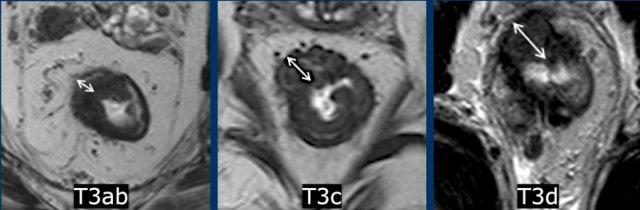

Phân loại phụ

giai đoạn T3 theo độ sâu xâm lấn

Trong khi sự liên quan về tiên lượng và điều trị của phân loại phụ T3 vẫn còn được tranh luận, mẫu báo cáo có cấu trúc của ESGAR vẫn tiếp tục sử dụng phân loại này:

Giai đoạn T3 sớm:

- T3a:<1 mm xâm lấn vượt quá lớp cơ thành

- T3b:1–5 mm mở rộng

Tiên tiến T3:

- T3c:5–15 mm kéo dài

- T3d:>15 mm mở rộng

Cân nhắc Chính

Bất kỳ khối u T3 nào có xâm lấn MRF—bất kể phân loại phụ—luôn được xem là nguy cơ cao.